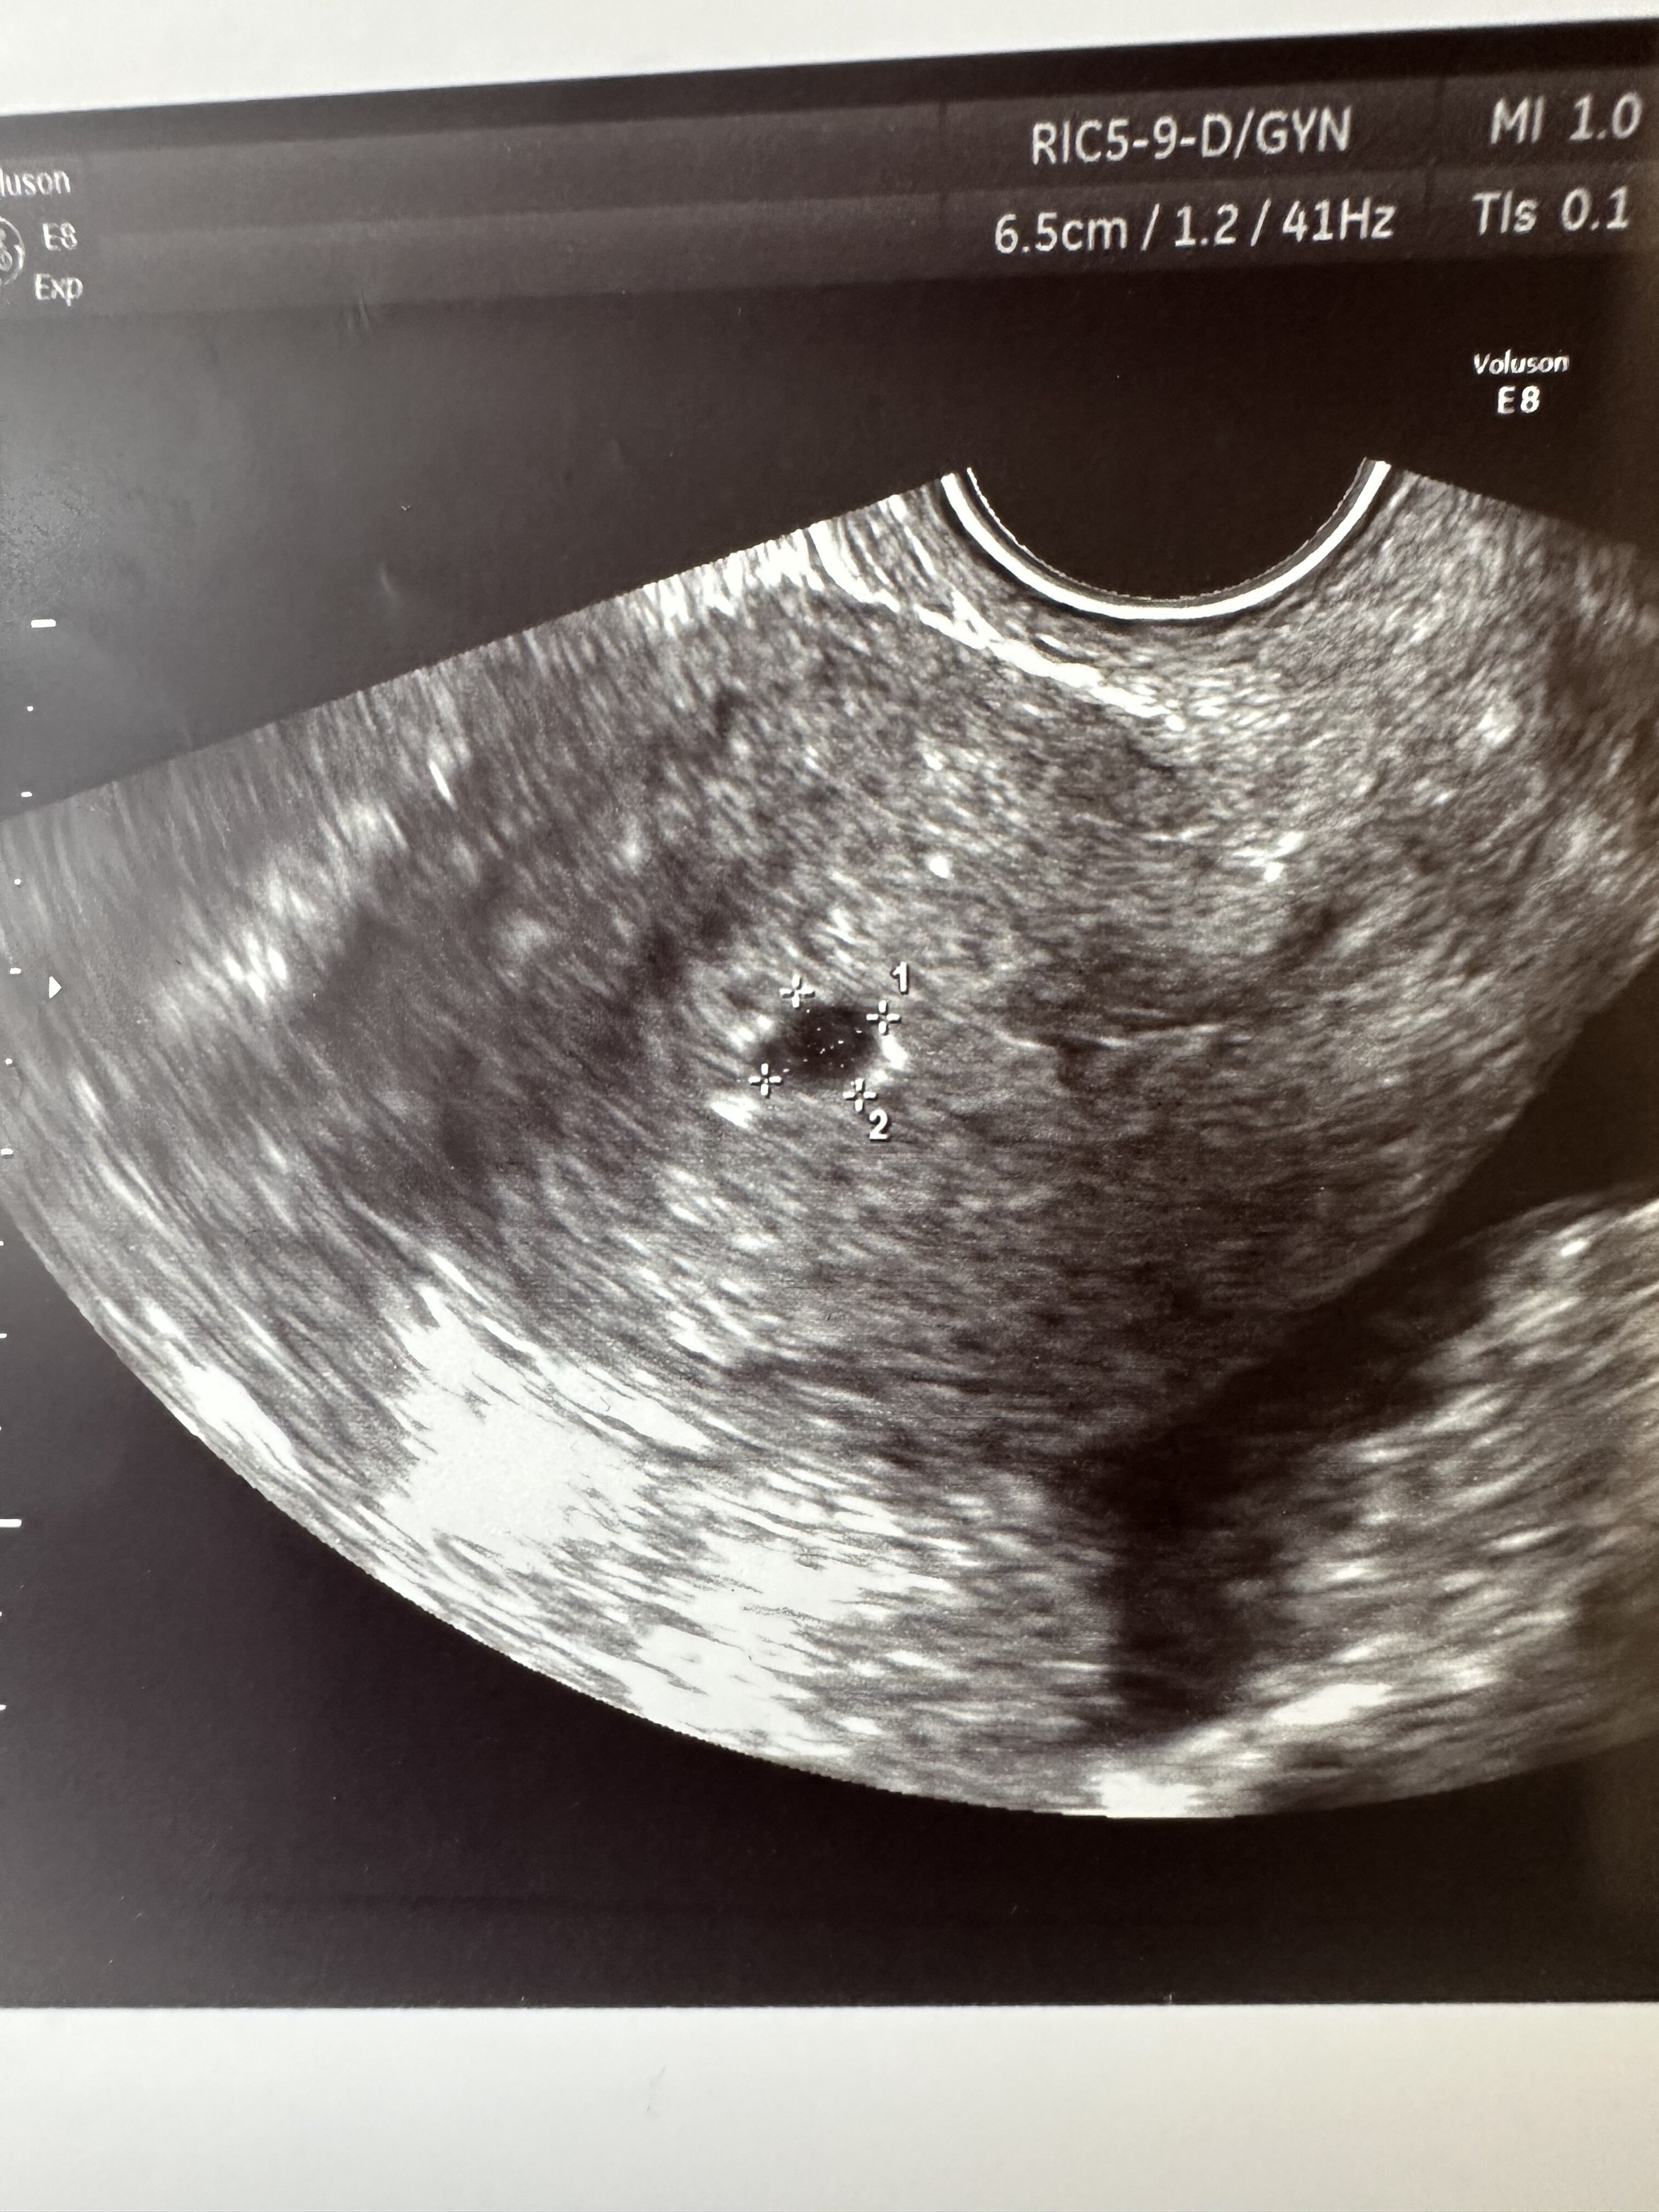

Kiedy najwcześniej jest sens iść na USG do ginekologa? Moja ginekolog kazała mi przyjść w okolicach 15.01 termin znalazłam u niej na 18.01. I zastanawiam się czy wcześniej umówić się do innego ginekologa na 9.01, będę wtedy wg miesiączki w 4tydz+5. Myślicie że lekarz będzie juz w stanie sprawdzić gdzie jest umiejscowiony pęcherzyk? Cały czas dokuczają mi bóle pleców, brzucha, nie mogę długo siedzieć i to też chciałabym skonsultować.

DziękiŻeby było widać pęcherzyk, to musi być około 1000 bety. Ja byłam 4+6 i pęcherzyk był elegancko widoczny.więc myślę że u Ciebie również w 4+5 powinno być widać jak na dłoni

9 stycznia powinien być widoczny pęcherzyk

18go będę w 6+0nie odwołuje tej wizyty bo docelowo chce u tej ginekolog prowadzić ciążę. Głównie właśnie że względu na te bóle chce podejść do gin, bo już momentami myślę czy nie są one spowodowane przez np. pozamaciczna...